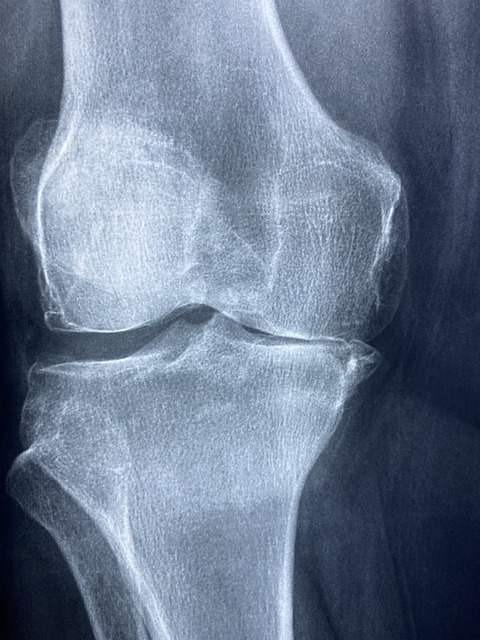

퇴행성 관절염 증상 이해하기

퇴행성 관절염은 관절의 연골이 서서히 손상되어 발생하는 만성적인 질환으로, 주로 노인이나 중년에 많이 발생합니다.

퇴행성 관절염의 치료는 증상의 완화, 기능 손상의 최소화, 그리고 생활 품질의 향상에 초점을 두고 있습니다. 비스테로이드계 항염증제(NSAIDs), 코르티코스테로이드 주사, 통증 완화제 등 다양한 약물 치료가 있습니다. 또한, 물리 치료나 운동 치료를 통해 근육을 강화하고 관절의 유연성을 유지할 수 있습니다. 심한 경우에는 수술적 치료를 고려할 수도 있습니다.